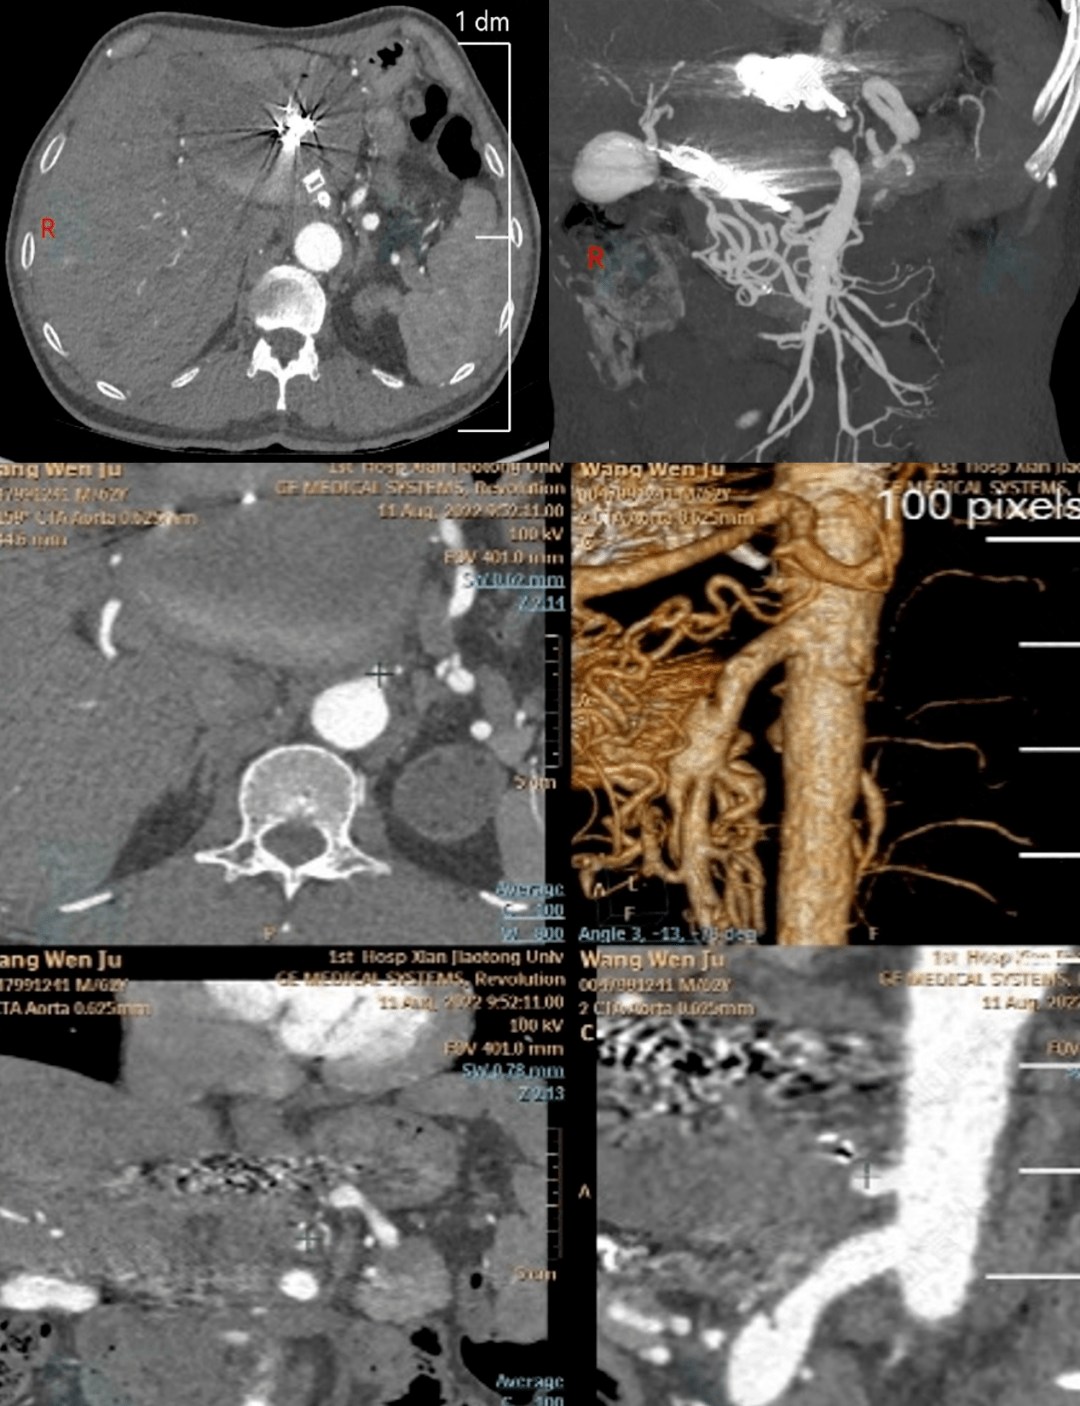

腹腔干动脉瘤

进食后腹痛数月"来院检查,腹部ct发现"腹主动脉瘤,腹腔干动脉瘤